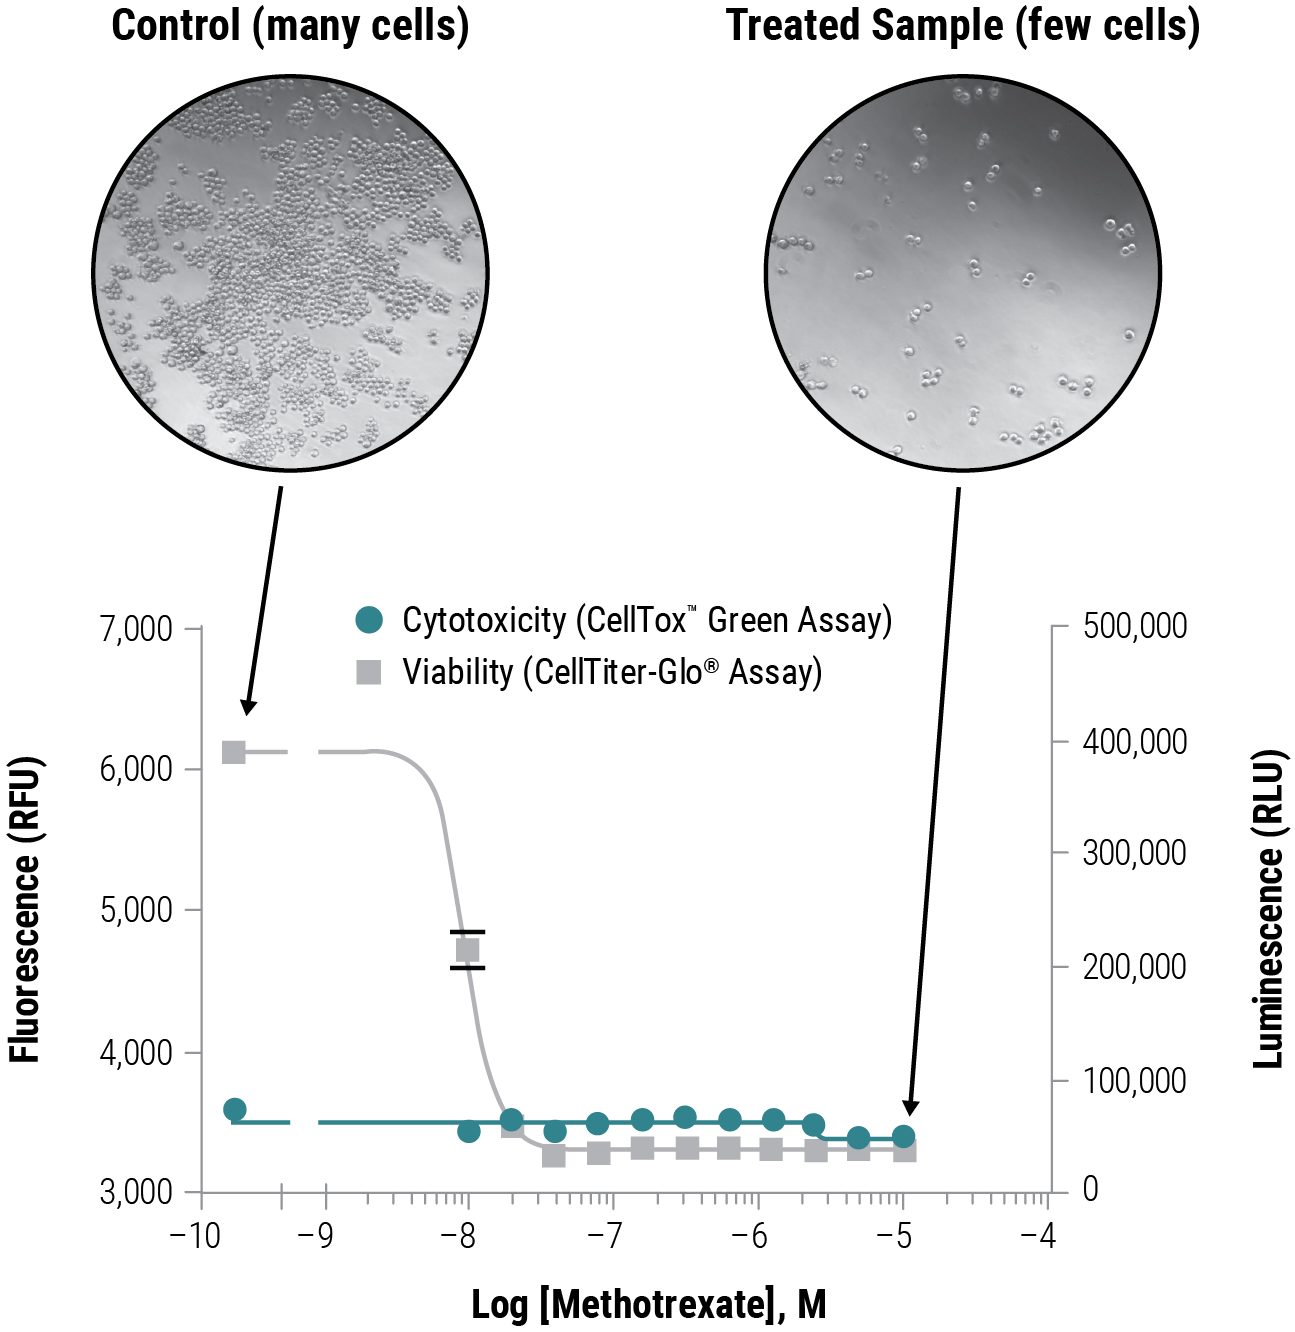

Differentiate Between Cytotoxic and Cytostatic Effects

In this example, K562 cells were exposed to Methotrexate, an anti-proliferative compound, for 72 hours. CellTox™ Green Dye was added to determine cytotoxicity, then CellTiter-Glo® Reagent was added to the same sample well for viability determination. A viability assay alone would have misreported the compound as cytotoxic due to less cells in the treated sample compared to the non-treated control, which continued to proliferate. Multiplexing with a cytotoxicity assay reveals no change in signal as a result of compromised membrane integrity, indicating growth inhibition and not cytotoxicity.